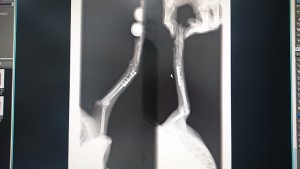

翌日は朝から早々に宿泊先をあとにして朝霧高原にあるドッグランへ行きました♪ ここのドッグランはお値段も安いですし設備も充実していてとても良かったです*^^* しかも月曜日だったので他のお客さんが1組いただけ♪ ビックリするような広さですしワンコ達も大満足だったようで。帰りの車ではみんな大爆睡で運転しているボクも眠くなったほどです・笑 アルテミスことチョコタンのあっくんを迎えてすぐに前足を折ってしまったのでこんなタイミングでの旅犬となりましたが、天候にも恵まれ充実した旅行となりました*^^*